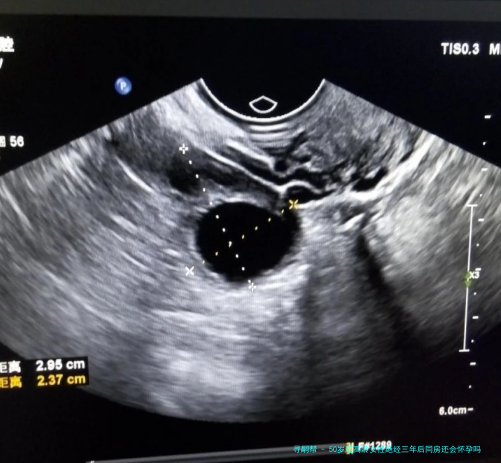

上一次看1个新闻说是大龄女性绝经后仍然怀孕,我就记忆挺不堪设想的,我原本来是不信的,但是我怕无数朋友都说是有这种案例存在的,但是我在想不是闭经随后,卵巢功效会下降吗,不是应该相比难以怀孕了呀,并且也不来大例假了,为什么还会出现这类情况呀,有姐妹知道上了50岁的超高龄女性,在绝经三个年头后又会怀孕吗?

上一次看1个新闻说是大龄女性绝经后仍然怀孕,我就记忆挺不堪设想的,我原本来是不信的,但是我怕无数朋友都说是有这种案例存在的,但是我在想不是闭经随后,卵巢功效会下降吗,不是应该相比难以怀孕了呀,并且也不来大例假了,为什么还会出现这类情况呀,有姐妹知道上了50岁的超高龄女性,在绝经三个年头后又会怀孕吗?